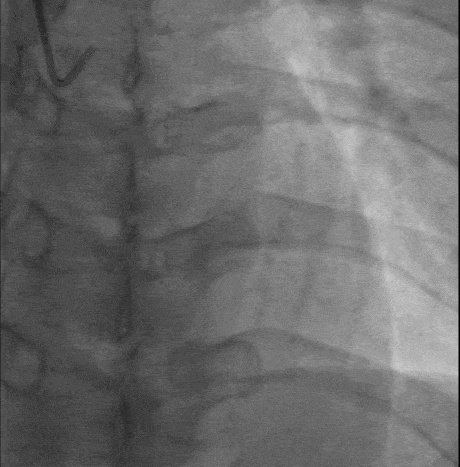

造影

两段闭塞 J-CTO score = 2(blunt tip/bending angle>45°)

无明显钙化,闭塞节段较短,首选对侧造影支持下正向策略